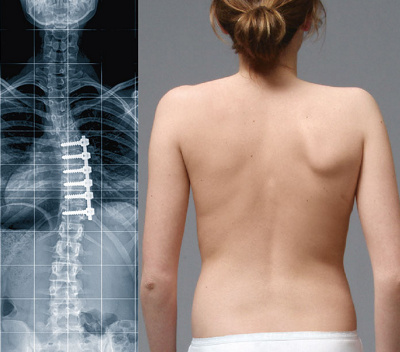

Röntgenbild und klinisches Foto zwei Jahre nach der Operation: Die Skoliose wurde mit einer Versteifung von nur fünf Bandscheiben korrigiert. Die kleine Operationsnarbe ist kaum erkennbar.